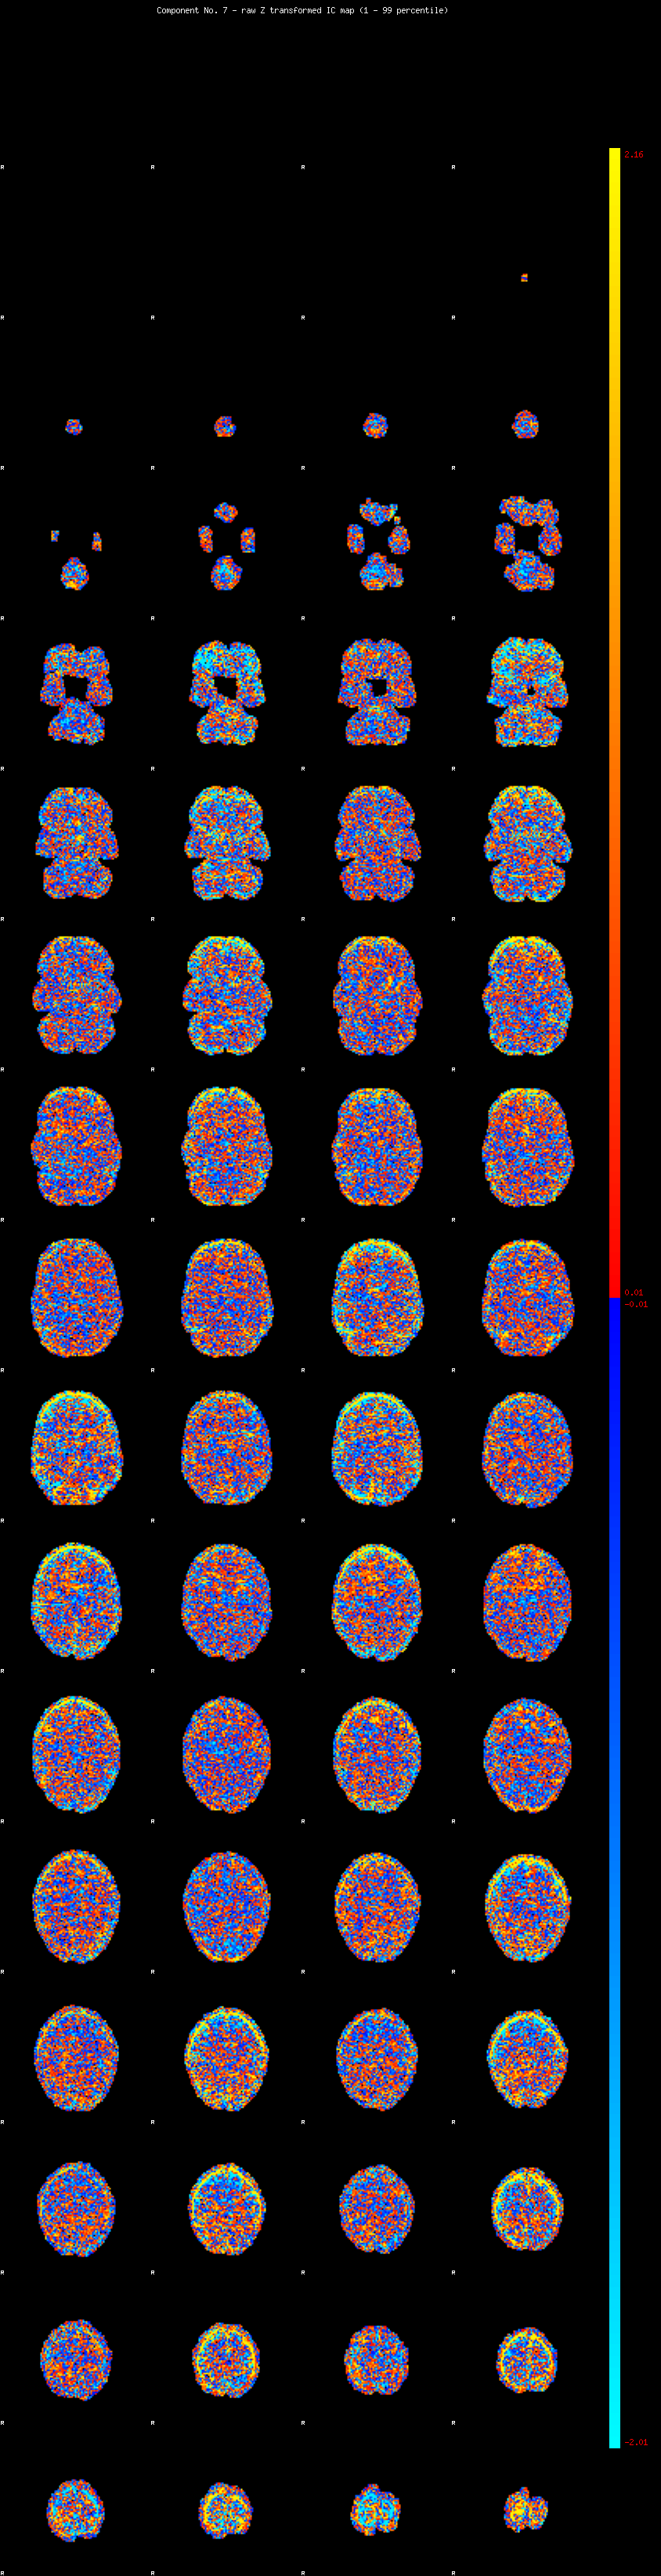

IC_7 Mixture Model fit

Means : -0.000000 3.056984 -2.775232

Vars : 1.000000 4.172254 1.488958

Prop. : 0.930154 0.041923 0.027923

This page produced automatically by MELODIC Version 3.14 - a part of FSL - FMRIB Software Library.